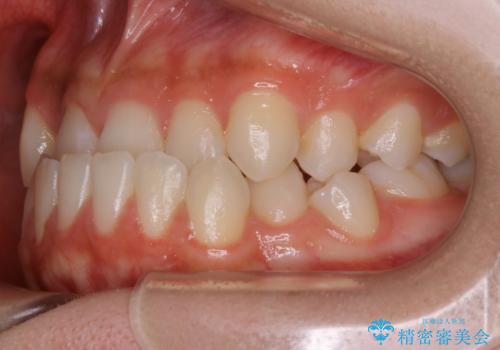

反対咬合(受け口)

本来、正常な噛み合わせの場合は上顎の前歯が下顎の前歯より前に覆いかぶさるように噛み込んでくる状態が理想的です。

それに対して「反対咬合(受け口)」の場合は、下顎の前歯が上顎の前歯より前に出てきてしまう状態を指します。

その原因は ①骨格的問題 ②機能的問題 の2つに大きく分かれます。

①に関しては外科的手術を併用した矯正治療を必要とする場合が多く、大学病院や専門の設備を備えた医院での治療が必要となります。

原因が②であった場合は、手術を必要とせず口腔内ではの位置を変えてあげるだけで噛み合わせや顔貌を変化させることができる場合があります。